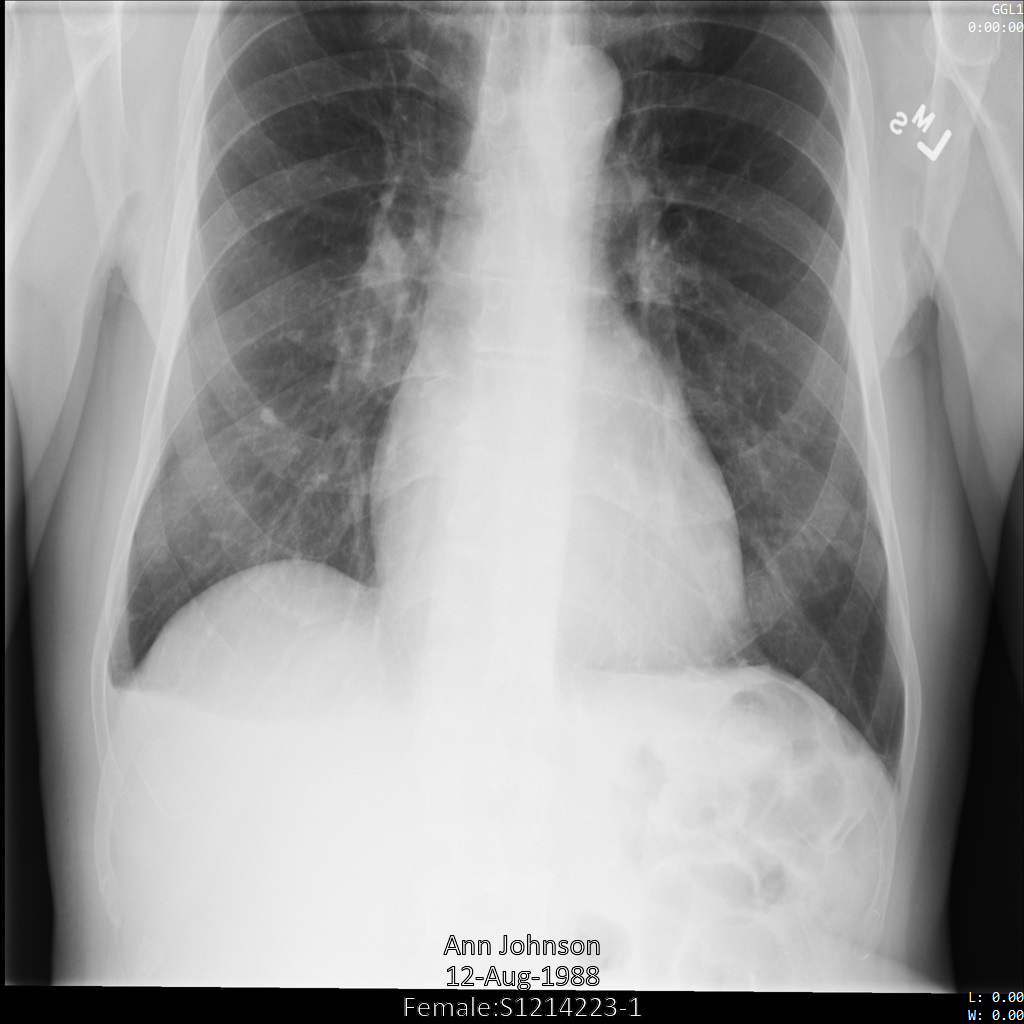

Depois de enviar a imagem para a Cloud Healthcare API, a imagem aparece

da seguinte forma. Das etiquetas fornecidas na lista de remoção, apenas PatientBirthDate

é removida na imagem, uma vez que é a única etiqueta da lista de remoção que

corresponde a metadados visíveis na imagem.

Embora o PatientBirthDate no canto superior da imagem tenha sido ocultado de acordo com a configuração na lista de remoção, as informações de saúde protegidas incorporadas na parte inferior da imagem permanecem. Para também remover o texto incorporado, consulte o artigo Ocultar texto incorporado em imagens.